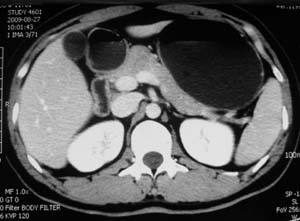

以下是引用子期在2010-3-19 20:47:00的发言:[br]血管畸形的ct增强应该有明显强化,本例并不相符合。本例双肾局部的略低密度影,累及肾盂,局部皮质明显变薄、内陷,增强扫描有轻度的强化,应考虑为炎性病变,患者为年轻男性,累及双肾的感染以结核较常见,可以没有明显的临床症状,尿中有时候也并不能查出什么;肾脓肿常有明显感染中毒症状,本例不符,另外一般的肾盂肾炎或肾小球肾炎通过小便就可确诊,其它还不能排除的是黄色肉芽肿性肾盂肾炎,然而单凭ct一般也很难鉴别。